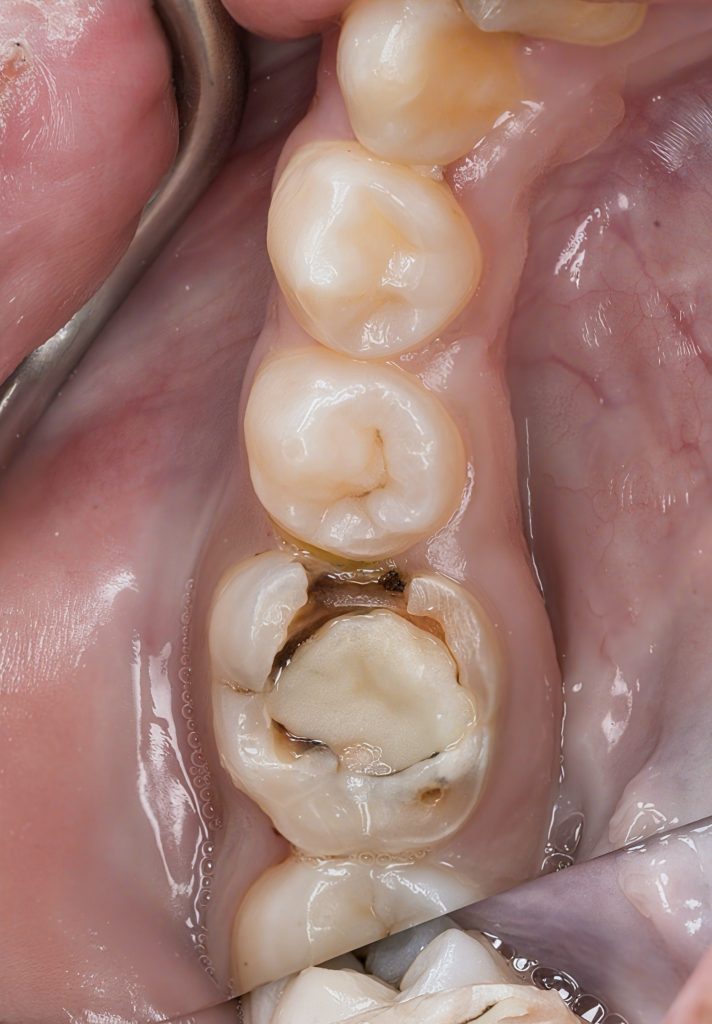

Patient presented with pain on biting and food packing around a previously treated molar. The radiograph showed under-prepared canals, missed anatomy, poor obturation density, and a failing coronal seal. Distal wall was undermined and cracked.

- Previous RCT failure: Voids, short fill on one canal, coronal leakage.

- Biomechanical compromise: Thin marginal ridges + undermined dentin.